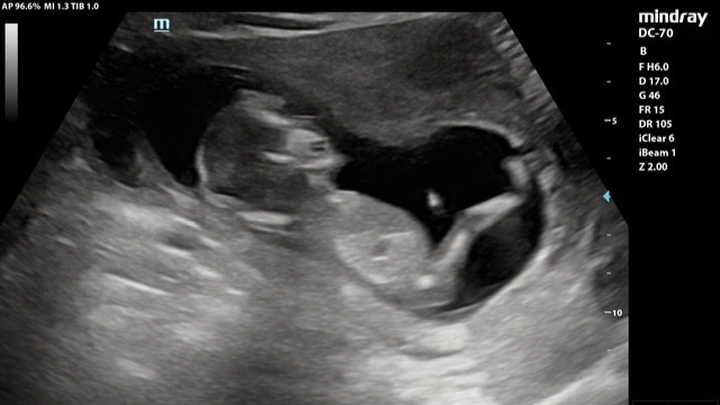

Since they said 'I do' in October 2024, Lys & Justice have been dreaming of the day they would welcome their first child. That dream became a reality when they found out they were expecting a baby boy, whom they’ve named Atlas. At 19 weeks gestation, Atlas is already living up to his name, showing incredible strength as he faces a significant medical journey. Recently, he was diagnosed with a lower urinary tract obstruction that is affecting his amniotic fluid levels and the development of his kidneys and lungs. While we have seen God move already, clearing the path of other complications like placenta previa, Atlas now needs a miracle through fetal intervention. We have been referred to the specialist team at Texas Children’s Hospital in Austin for life-saving surgery. As a young couple starting out, the financial weight of these procedures is overwhelming. With medical costs estimated at $60,000, we are reaching out to our 'village' to help give Atlas the best possible chance at life.